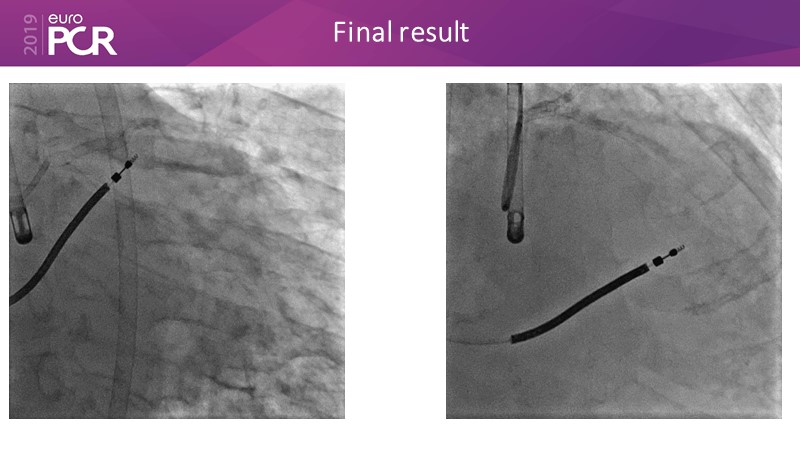

Distal left main stenosis: how to treat optimally with dedicated bifurcation stent BiOSS Lim C. Case-based session

Consult this session to learn more about the multiple technological options with dedicated bifurcation stent for complex left main bifurcation lesions, and the applicability of this stent for the different clinical presentations.

- To learn about multiple technological options with dedicated bifurcation stent for complex left main bifurcation lesions